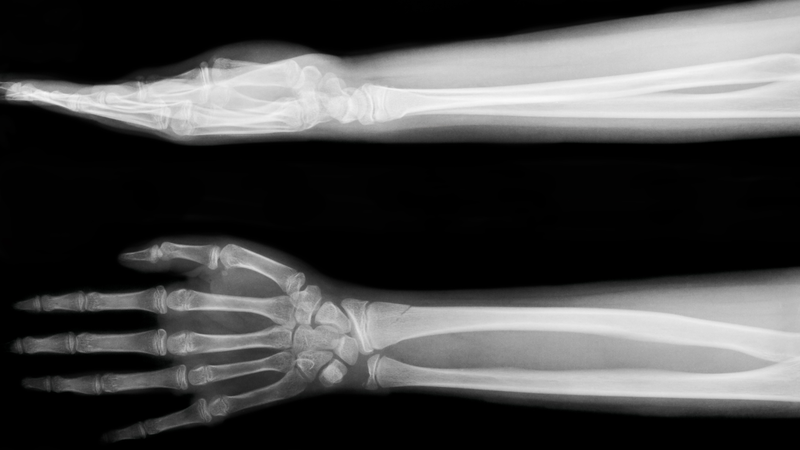

Khi nào cần chụp X-quang chi trên? Trường hợp nào không nên chụp?

Khi nào cần chụp X-quang chi trên và trường hợp nào không nên chụp là những vấn đề nhiều người quan tâm khi gặp các triệu chứng liên quan đến xương khớp vùng tay. Việc hiểu rõ thời điểm cần thực hiện cũng như những trường hợp không nên chụp sẽ giúp bạn chủ động hơn khi thăm khám, hạn chế lo lắng và đảm bảo quá trình chẩn đoán diễn ra an toàn, chính xác hơn.

Chụp X-quang chi trên là phương pháp chẩn đoán hình ảnh phổ biến giúp phát hiện các tổn thương xương, khớp ở tay và vai. Tuy nhiên, không phải ai cũng cần thực hiện kỹ thuật này. Hiểu rõ khi nào nên chụp, đối tượng chống chỉ định và quy trình chụp X-quang chi trên sẽ giúp bạn chủ động thăm khám, đảm bảo an toàn và nâng cao hiệu quả chẩn đoán.

Chụp X-quang chi trên là kỹ thuật chẩn đoán hình ảnh sử dụng tia X để quan sát cấu trúc xương, khớp và một phần mô mềm từ vai đến bàn tay. Phương pháp này giúp phát hiện các vấn đề như gãy xương, trật khớp, viêm khớp, khối u hay dị vật, hỗ trợ bác sĩ đưa ra chẩn đoán và hướng điều trị phù hợp. Thủ thuật diễn ra nhanh, hầu như không gây đau và đảm bảo an toàn khi thực hiện đúng chỉ định.

Bác sĩ sẽ chỉ định chụp X-quang chi trên khi nghi ngờ chấn thương ở tay